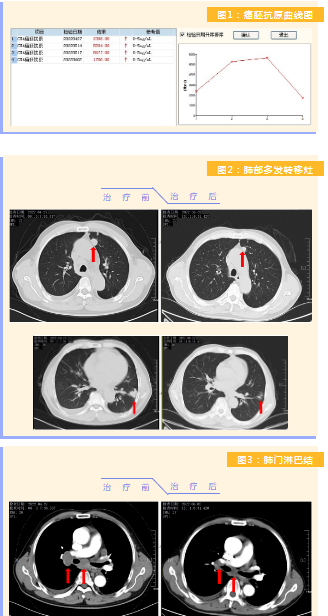

患者完成1周期治療后,上腹部疼痛癥狀基本消失,梗阻性黃疸癥狀緩解,腫瘤指標(biāo)下降(圖1),肺部多發(fā)轉(zhuǎn)移灶消失和縮小(圖2),雙肺門淋巴結(jié)縮?。▓D3),肝臟多發(fā)轉(zhuǎn)移灶縮小(圖4)。